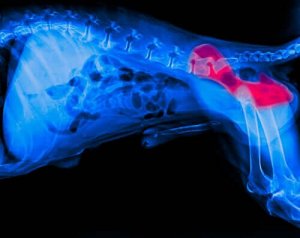

Dysplasi er en tilstand som påvirker hofteleddene og området rundt. Det er forårsaket av en misdannelse i lårhodet og det tilsvarende hofteleddet. Når dette skjer, kan leddet begynne å bli dårligere og forårsake ubehag og halthet.

Hofteleddsdysplasi hos hunder begynner å utvikle seg når hunden er rundt 4 eller 5 måneder gammel, og blir verre etter hvert som bekkenet vokser. Hofteleddsdysplasi klassifiseres i henhold til alvorlighetsgrad, prognose og behandling.

Hofteleddsdysplasi har en rekke symptomer hos hunder. De vanligste inkluderer halthet, vanskeligheter med å reise seg eller en hund som hele tiden holder seg på beina. Så hvis du merker noen av disse symptomene, må du oppsøke en veterinær, som vil foreta røntgen for å bekrefte diagnosen.